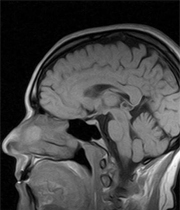

Un estudio hecho por el investigador Miguel Burgaleta, de la Universidad Pompeu Fabra de Barcelona, apuntó que los hombres poseen un cerebro 10 por ciento más grande que el de las mujeres, lo que les habilita para poseer un 16 por ciento más de neuronas.

Imagen"El hombre tiene más neuronas dedicadas al razonamiento espacial. El cerebro de ellas es más eficiente, necesita menos energía y es mejor para las tareas verbales", señaló Burgaleta, según consignó el sitio de Antena3.

El reporte confirmó la característica, pero al mismo tiempo advirtió que esto no deja a los hombres en una mejor posición en términos de inteligencia.

Ellas pueden realizar varias actividades al mismo tiempo, ya que poseen un mayor número de conexiones neuronales que las habilitan para eso. Su cerebro es de menor tamaño, necesita de menos energía y sus conexiones de materia blanca son más compactas.

El estudio también apunta que la evolución actual del cerebro tiene que ver con las primeras modificaciones del mismo, cuando el hombre salía a cazar desarrolló su cerebro para interactuar con su entorno, sin perderse y ocupar posiciones estratégicas para conseguir sus objetivos.

Esto, en tanto que, la densidad neuronal de las féminas posibilita la facilidad para expresar sus emociones, comprender de mejor manera la comunicación no verbal y potenciar su empatía con otras personas, característica fue desarrollada por las madres en el Paleolítico (más de 10.000 años atrás).